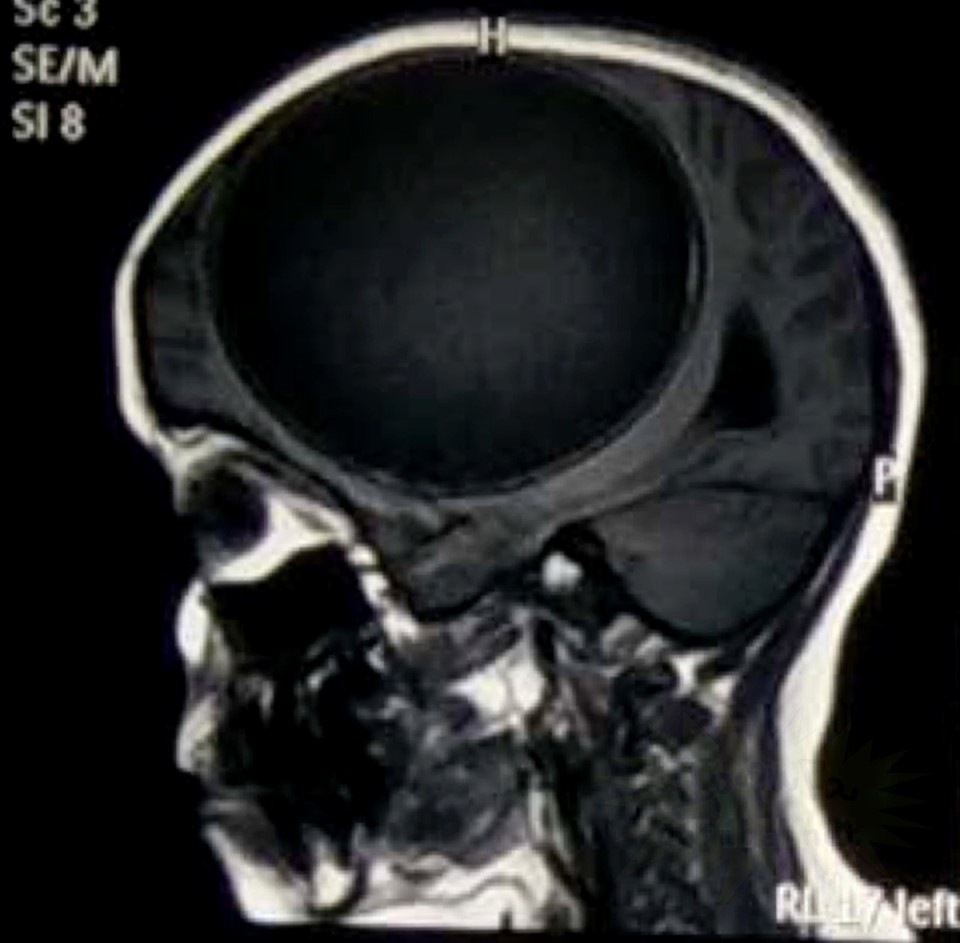

gif_animation インドにて、12歳の女の子の身体(脳部分)から、寄生虫の卵、675gが取り出された。頭痛に苦しんでいたという女の子。感染源は不明である。[7]images